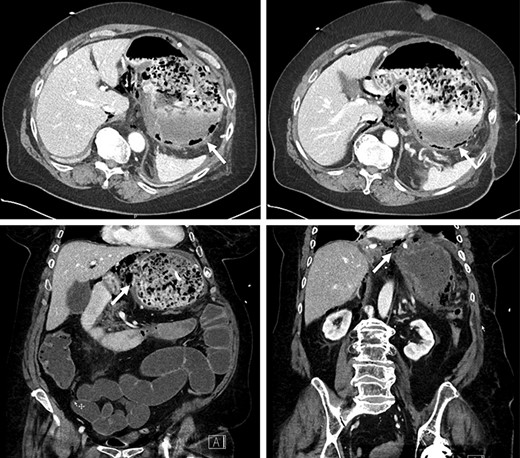

The patient arrived intubated in a stable condition. She was put on wide-spectrum antibiotherapy of piperacillin/tazobactam. Thoracic and abdominopelvic CT scans were performed at our institution and showed pneumatosis in the posterior wall of the gastric cavity as well as in the antrum wall and the lesser curvature, suggestive of gastric ischemia (Fig. 1). There was no evidence of arterial or venous thrombosis of major abdominal and thoracic vessels. The gastric injury was extensive, and the stomach deemed unsalvageable. The patient underwent a total gastrectomy with Roux-en-Y esophagojejunostomy. A feeding jejunostomy was installed intraoperatively.

Pneumatosis in the posterior wall and lesser curvature of the gastric cavity on CT scan.